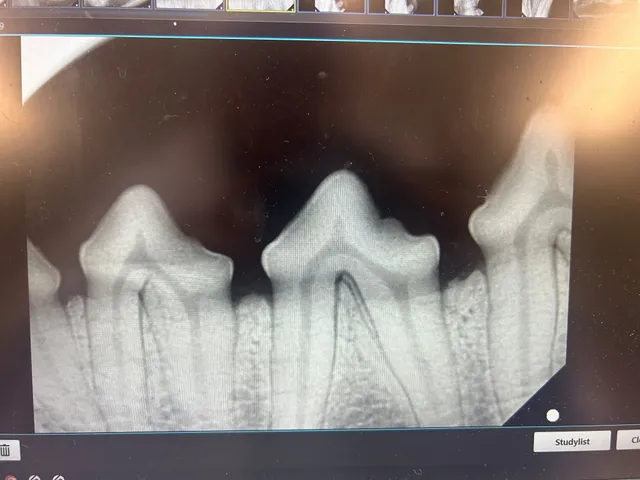

Dental Care:

Dental health plays a major role in our pets overall well being, We provide Comprehensive Oral Health Assessment and Treatment (COHAT) including, dental radiographs, cleaning, polishing and extractions when needed. Regular dental care helps prevent pain, infection, and other health issues linked to dental disease.

dental radiographs